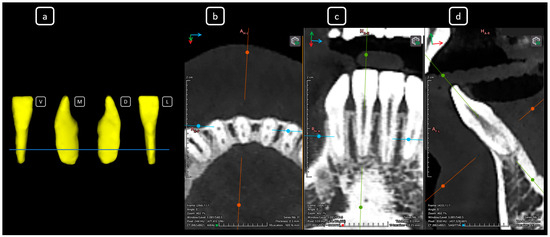

Cone beam computed tomography (CBCT) is a valuable diagnostic tool for evaluating the upper airway and maxillofacial region. This report demonstrates the clinical value of CBCT in identifying significant anatomical variations in endodontics, incidentally detected on a non-endodontic CBCT scan. A 23-year-old female patient underwent CBCT imaging at the Faculty of Dentistry-UJED to evaluate her upper airway. CBCT imaging revealed a unique, complex, and unusual anatomy of mandibular root canals, characterized by Vertucci’s type III root canals in the anterior sextant and co-occurrence of bilateral C-shaped mandibular second molars (type C2 according to Fan’s classification). No therapeutic interventions were initiated due to the patient’s asymptomatic status. CBCT imaging is a valuable tool for integrated diagnostic approaches, underscoring its role in thorough patient management. The integration of multidisciplinary interpretation of CBCT data can enhance diagnostic accuracy and optimize patient records and management, emphasizing the importance of collaborative efforts between radiologists, clinicians, and endodontists. Documenting and sharing such findings can increase awareness of rare anatomical variations, facilitating detection and contributing to medical knowledge. Full article

Figure 1